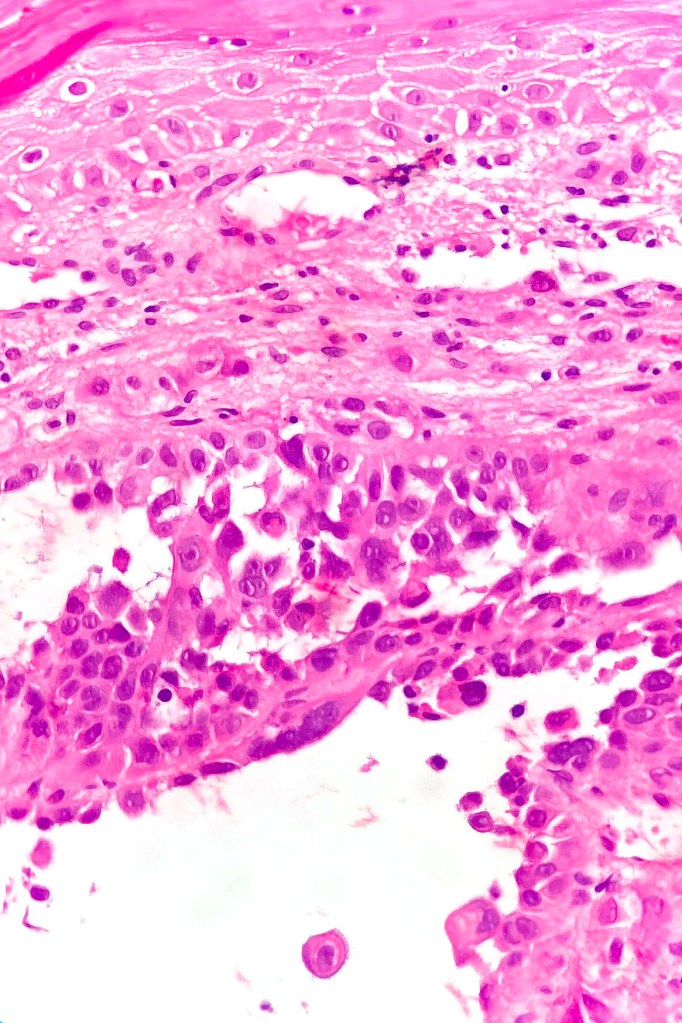

•Acantholysis gives rise to a pseudoglandular appearance

•Often well differentiated

•Variable pleomorphism & mitotic activity

•Absence of epithelial mucin